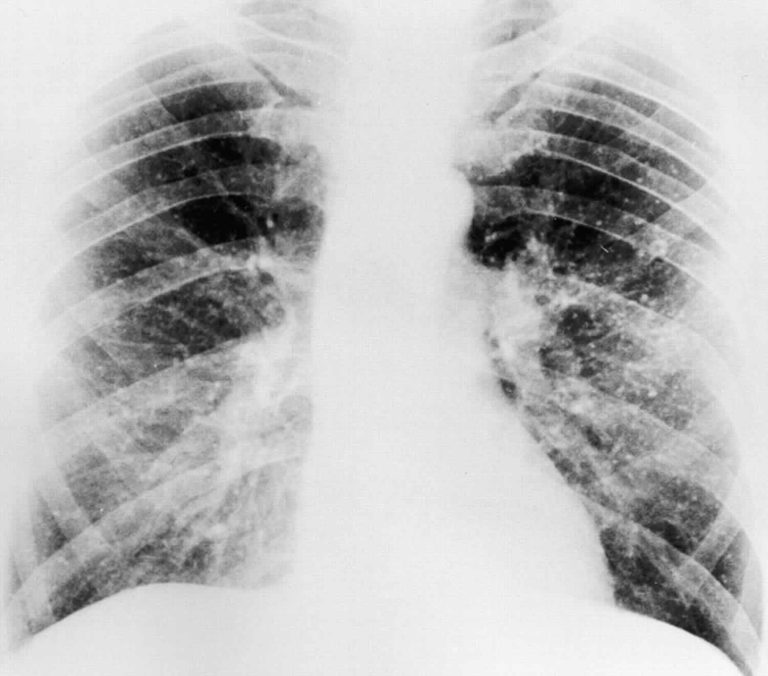

From thorax.bmj.com

Metastatic pulmonary calcification ‘crazy paving’ pattern Thorax Popcorn Calcification Of Lung (i) central dense nidus (ii) diffuse solid (iii) laminated (iv) popcorn (v) punctate and (vi) dendriform. 2 pulmonary chondroid hamartomas measuring over 10 cm are very rare. They may show varying patterns of. Popcorn calcications are a conglomerate of calcications that occupy most of the peripheral lung node (↑). This pattern of calcification is commonly referred to as “popcorn” calcification,. Popcorn Calcification Of Lung.